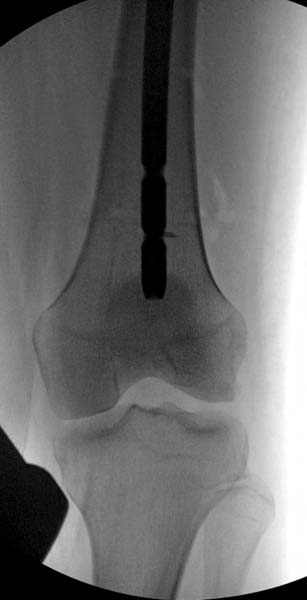

Около 11.00 вечера больная переведена в реанимацию, без сознания, но стабильная.. На третьий день провели стабилизацию перелома бедра антеградным остеосинтезом.

Закрытый БИОС решает множественные проблемы связанные с лечением переломов, но проблема дистальной блокировки без рентгена до сих пор остается нерешенной. Рекламированные производителями приспособления для дистальной блокировки из-за различной кривизны кости не эффективны или стоит очень дорого (Smith&Nephew SureLock). Задержка операции из-за блокировки не всегда удовлетворяет, и многих вынуждает искать альтернативные методы фиксации. С результатами таких действий, остеомиелитом и несращениями, встречаемся в ежедневной жизни..